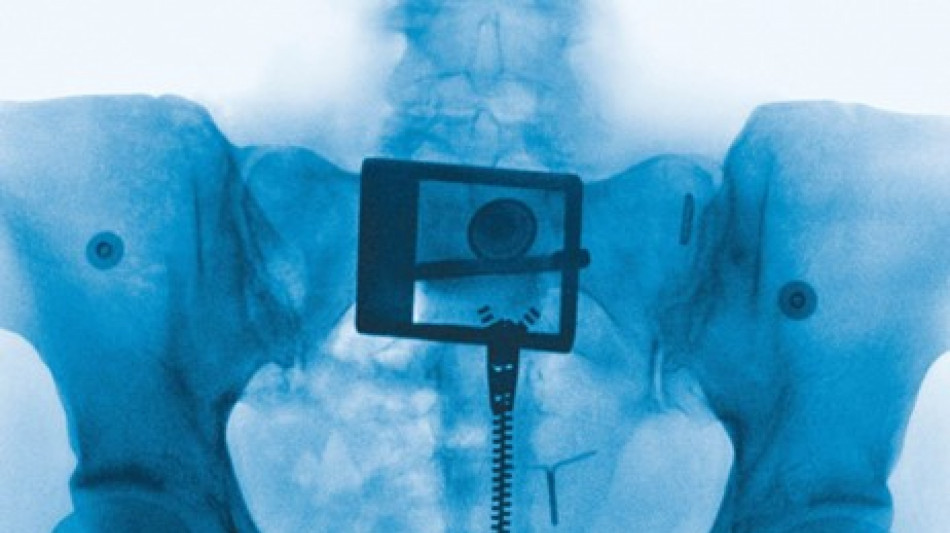

Studio sul dna di Hitler, 'aveva organi sessuali non sviluppati'